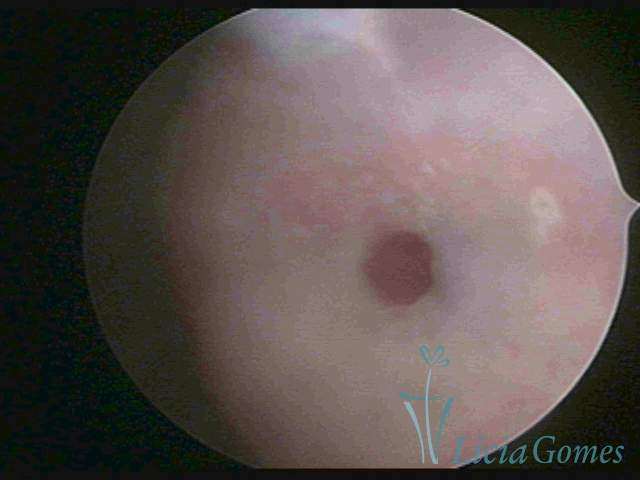

Terceira porção ou porção superior

Apresenta a mucosa com a superfície lisa e pouco vascularizada até a altura do orifício interno